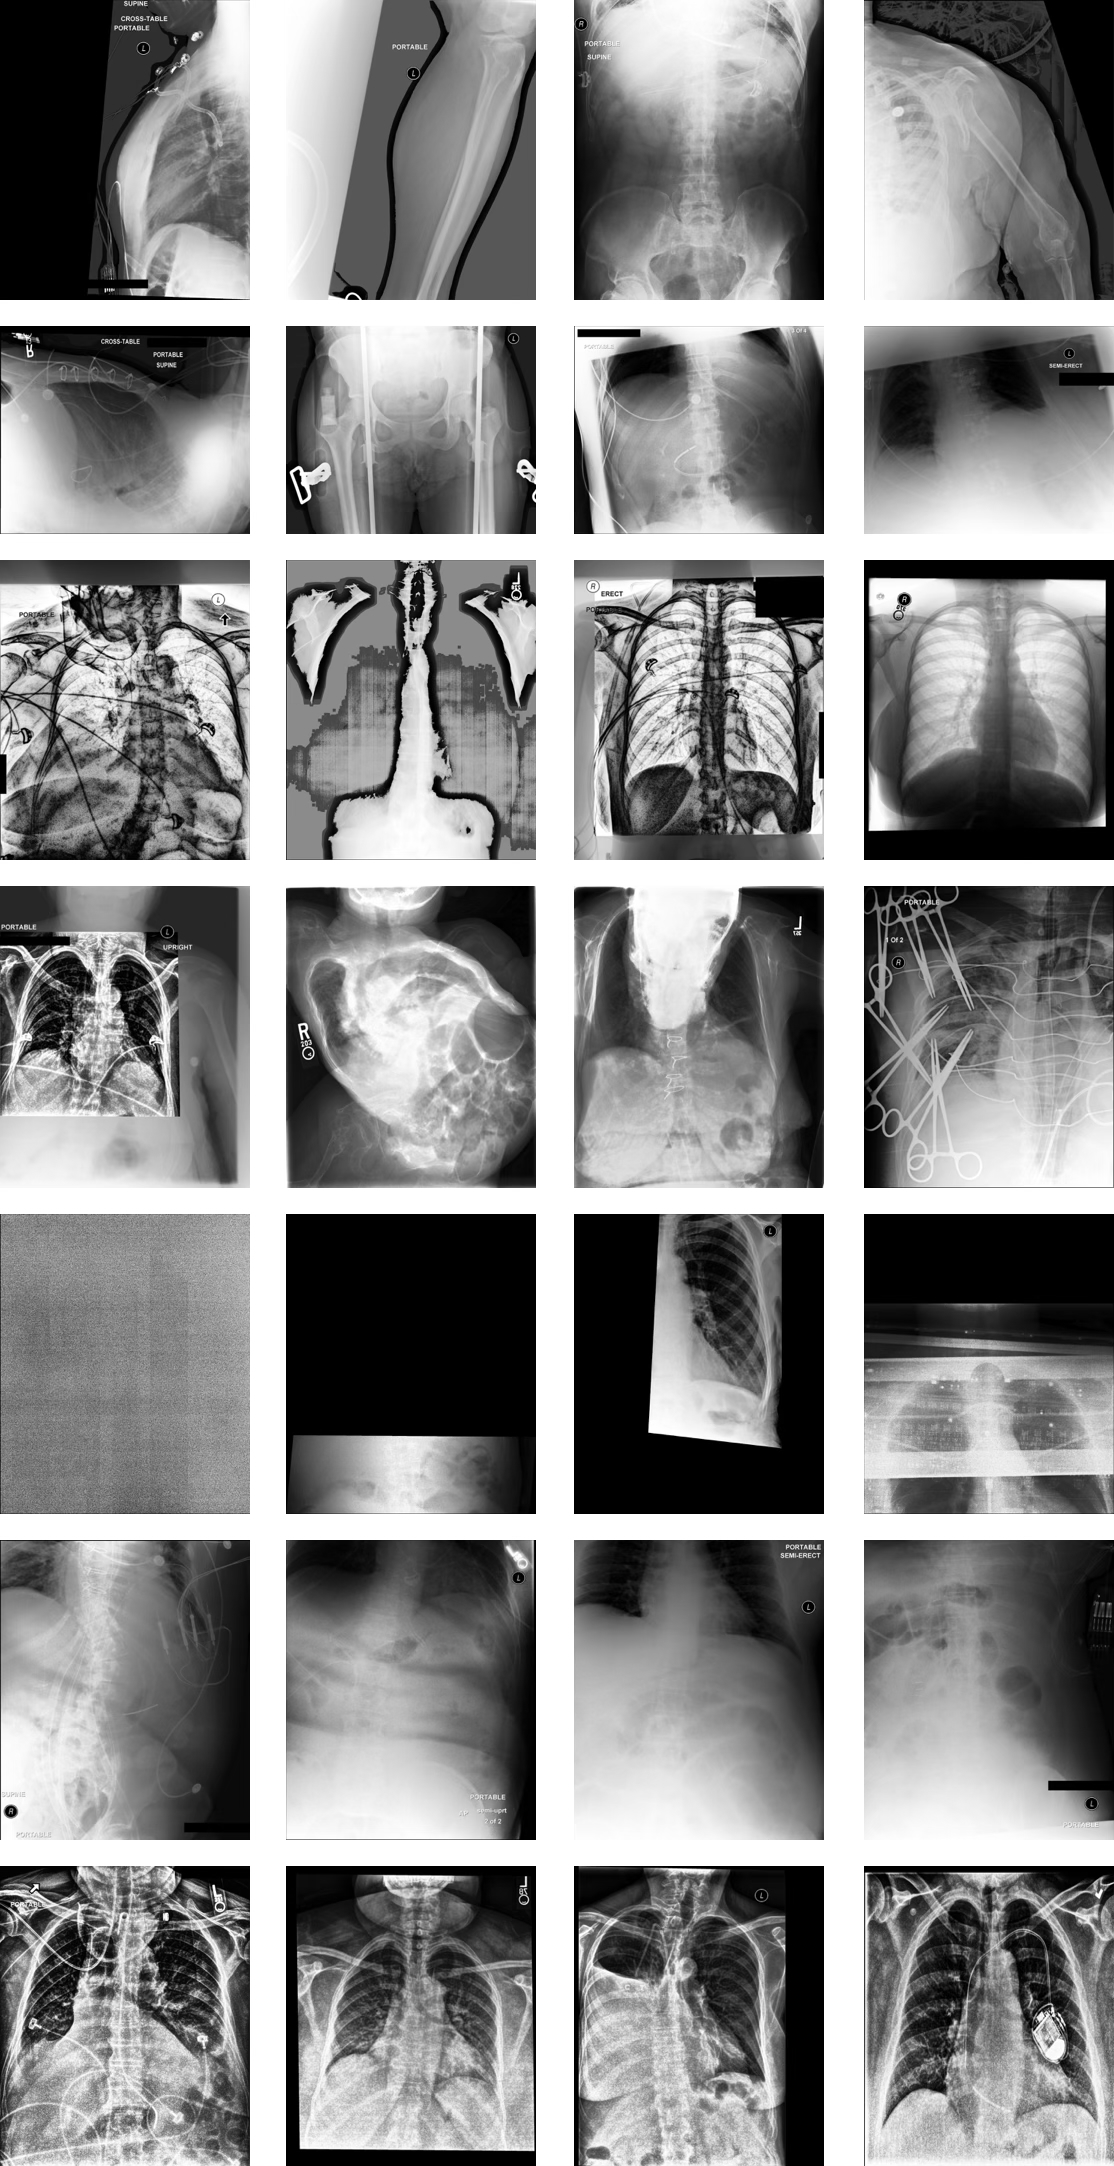

This step serves as a robust first-pass filter that eliminates obviously invalid images based on anatomical structure segmentation. See Figure 16, Rows 1–5 for representative examples.

Step 2: Anatomical Position-Based Filtering (Heart Mask Heuristic)

For the remaining images, we apply a heuristic based on the vertical position of the heart mask, one of the reliably segmented structures from CXAS.

We compute the vertical ratio of the image above and below the heart mask. If the heart is located disproportionately high in the image (i.e., a large portion of the image appears below the heart), this often indicates that the image contains substantial abdominal or pelvic anatomy.

These images are excluded based on this anatomical positioning heuristic. See Figure 16, Row 6 for representative examples.

Step 3: Gradient-Based Filtering to Remove Post-Processing Artifacts

Even after anatomical filtering, some images suffer from post-processing artifacts, such as low contrast or improper windowing adjustments that obscure anatomical structures.

To detect such cases, we compute the average edge strength across each image using gradient magnitude:

• Horizontal and vertical edge maps are computed using the Sobel operator.

• Gradient magnitude is calculated to quantify edge strength.

• The mean gradient magnitude across the image is used as a filtering metric.

Images with abnormally low edge strength typically lack sufficient anatomical contrast and are deemed visually uninformative. These are removed during this step. See Figure 16, Row 7 for representative examples.

After applying the global filtering steps, we excluded 7,587 images, resulting in 235,747 high-quality PA and AP chest X-rays. This corresponds to 3.12% of the images initially labeled as PA or AP in the metadata being removed due to quality concerns.

Figure 16: Representative Examples of Globally Filtered Images. Rows 1–5: Images removed due to a small number of segmented anatomical structures using CXAS (Step 1). Row 6: Image removed due to abnormal anatomical positioning of heart mask (Step 2). Row 7: Image removed due to post-processing artifacts and low gradient strength (Step 3).